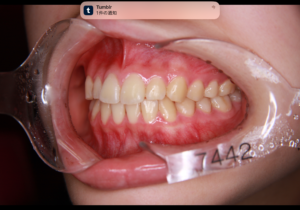

カマクラデントフェイシャルオーソピディクス・山本歯科・矯正長期安定症例